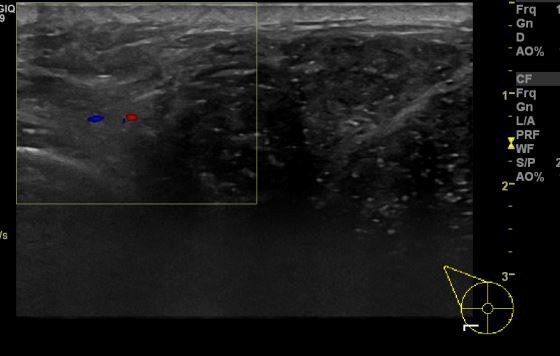

상기환자   우측 유방에 만져지는 멍울과 분비물로 내원한 20대 여성 분으로

우측 만져지는 멍울 조직검사 시행하여 우측 침윤성 유관암 진단 되었습니다.